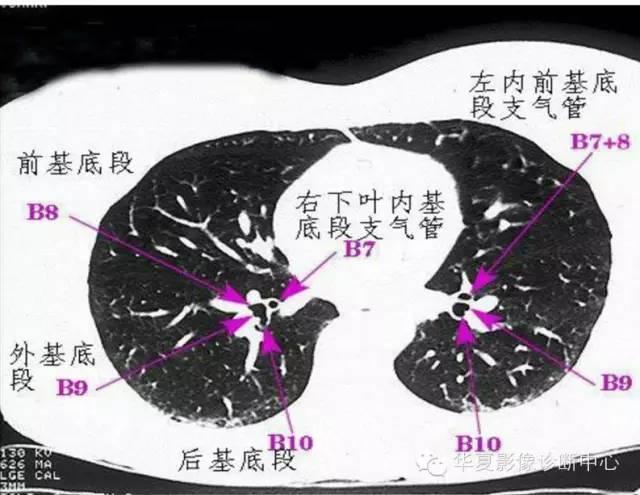

胸部ct 肺窗

图片尺寸1080x1920